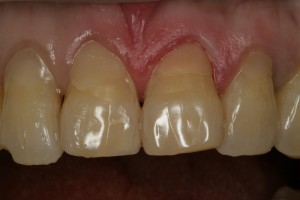

치료가 끝난 후의 사진입니다. 기존의 다른 치아 색깔과 조화로운 레진 치료가 되었습니다.